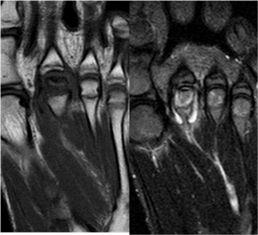

Las imágenes corresponden a: plano axial T1, plano coronal STIR y plano sagital STIR. En las mismas se visualiza un engrosamiento de la cortical medial del segundo metatarsiano, acompañado de edema óseo y edema de las partes blandas adyacentes.

Ante estos hallazgos el primer diagnóstico a considerar es el de Fractura por Stress. Sin embargo, ante el cuadro clínico es importante tener en cuenta otros dos diagnósticos diferenciales de importancia: la Sesamoiditis y la Enfermedad de Freiberg (infarto óseo de la cabeza del segundo metatarsiano), visibles en las siguientes imágenes: